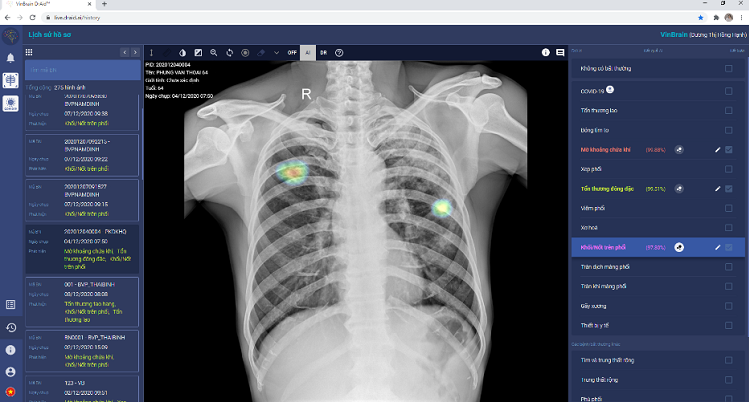

Theo đó, DrAid hỗ trợ bác sĩ chẩn đoán các dấu hiệu bất thường và bệnh lý về tim-phổi-xương dựa trên hình ảnh X-quang ngực. Hệ thống DrAid gồm 3 phần: ứng dụng trí tuệ nhân tạo (AI), nền tảng điện toán đám mây và hệ sinh thái các thiết bị di động. Đến tháng 11/2020, DrAid đã hỗ trợ chẩn đoán 18 dấu hiệu bất thường trong vòng 5 giây với độ chính xác trên 88%. Đồng thời, tự động đưa ra báo cáo y tế có khoanh vùng, bản đồ nhiệt và đo kích thước chính xác tại điểm bất thường. DrAid là sản phẩm AI đầu tiên tại Việt Nam có bộ dữ liệu lớn 1,3 triệu hình ảnh X-quang với hơn 250 nghìn hình ảnh đã được gán nhãn và bộ dữ liệu Covid-19 lớn thứ hai toàn cầu (7.490 hình ảnh dương tính của bệnh nhân COVID-19).

Danh mục định nghĩa các dấu hiệu bất thường và bệnh lý của DrAid được phối hợp thực hiện bởi Đại học Stanford, Mỹ và đội ngũ chuyên gia, bác sĩ chẩn đoán hình ảnh (CĐHA) hàng đầu Việt Nam.

Với dịch COVID-19, hệ thống còn tự động đưa ra cảnh báo, kể cả các trường hợp không có triệu chứng hoặc tổn thương phổi nhẹ.